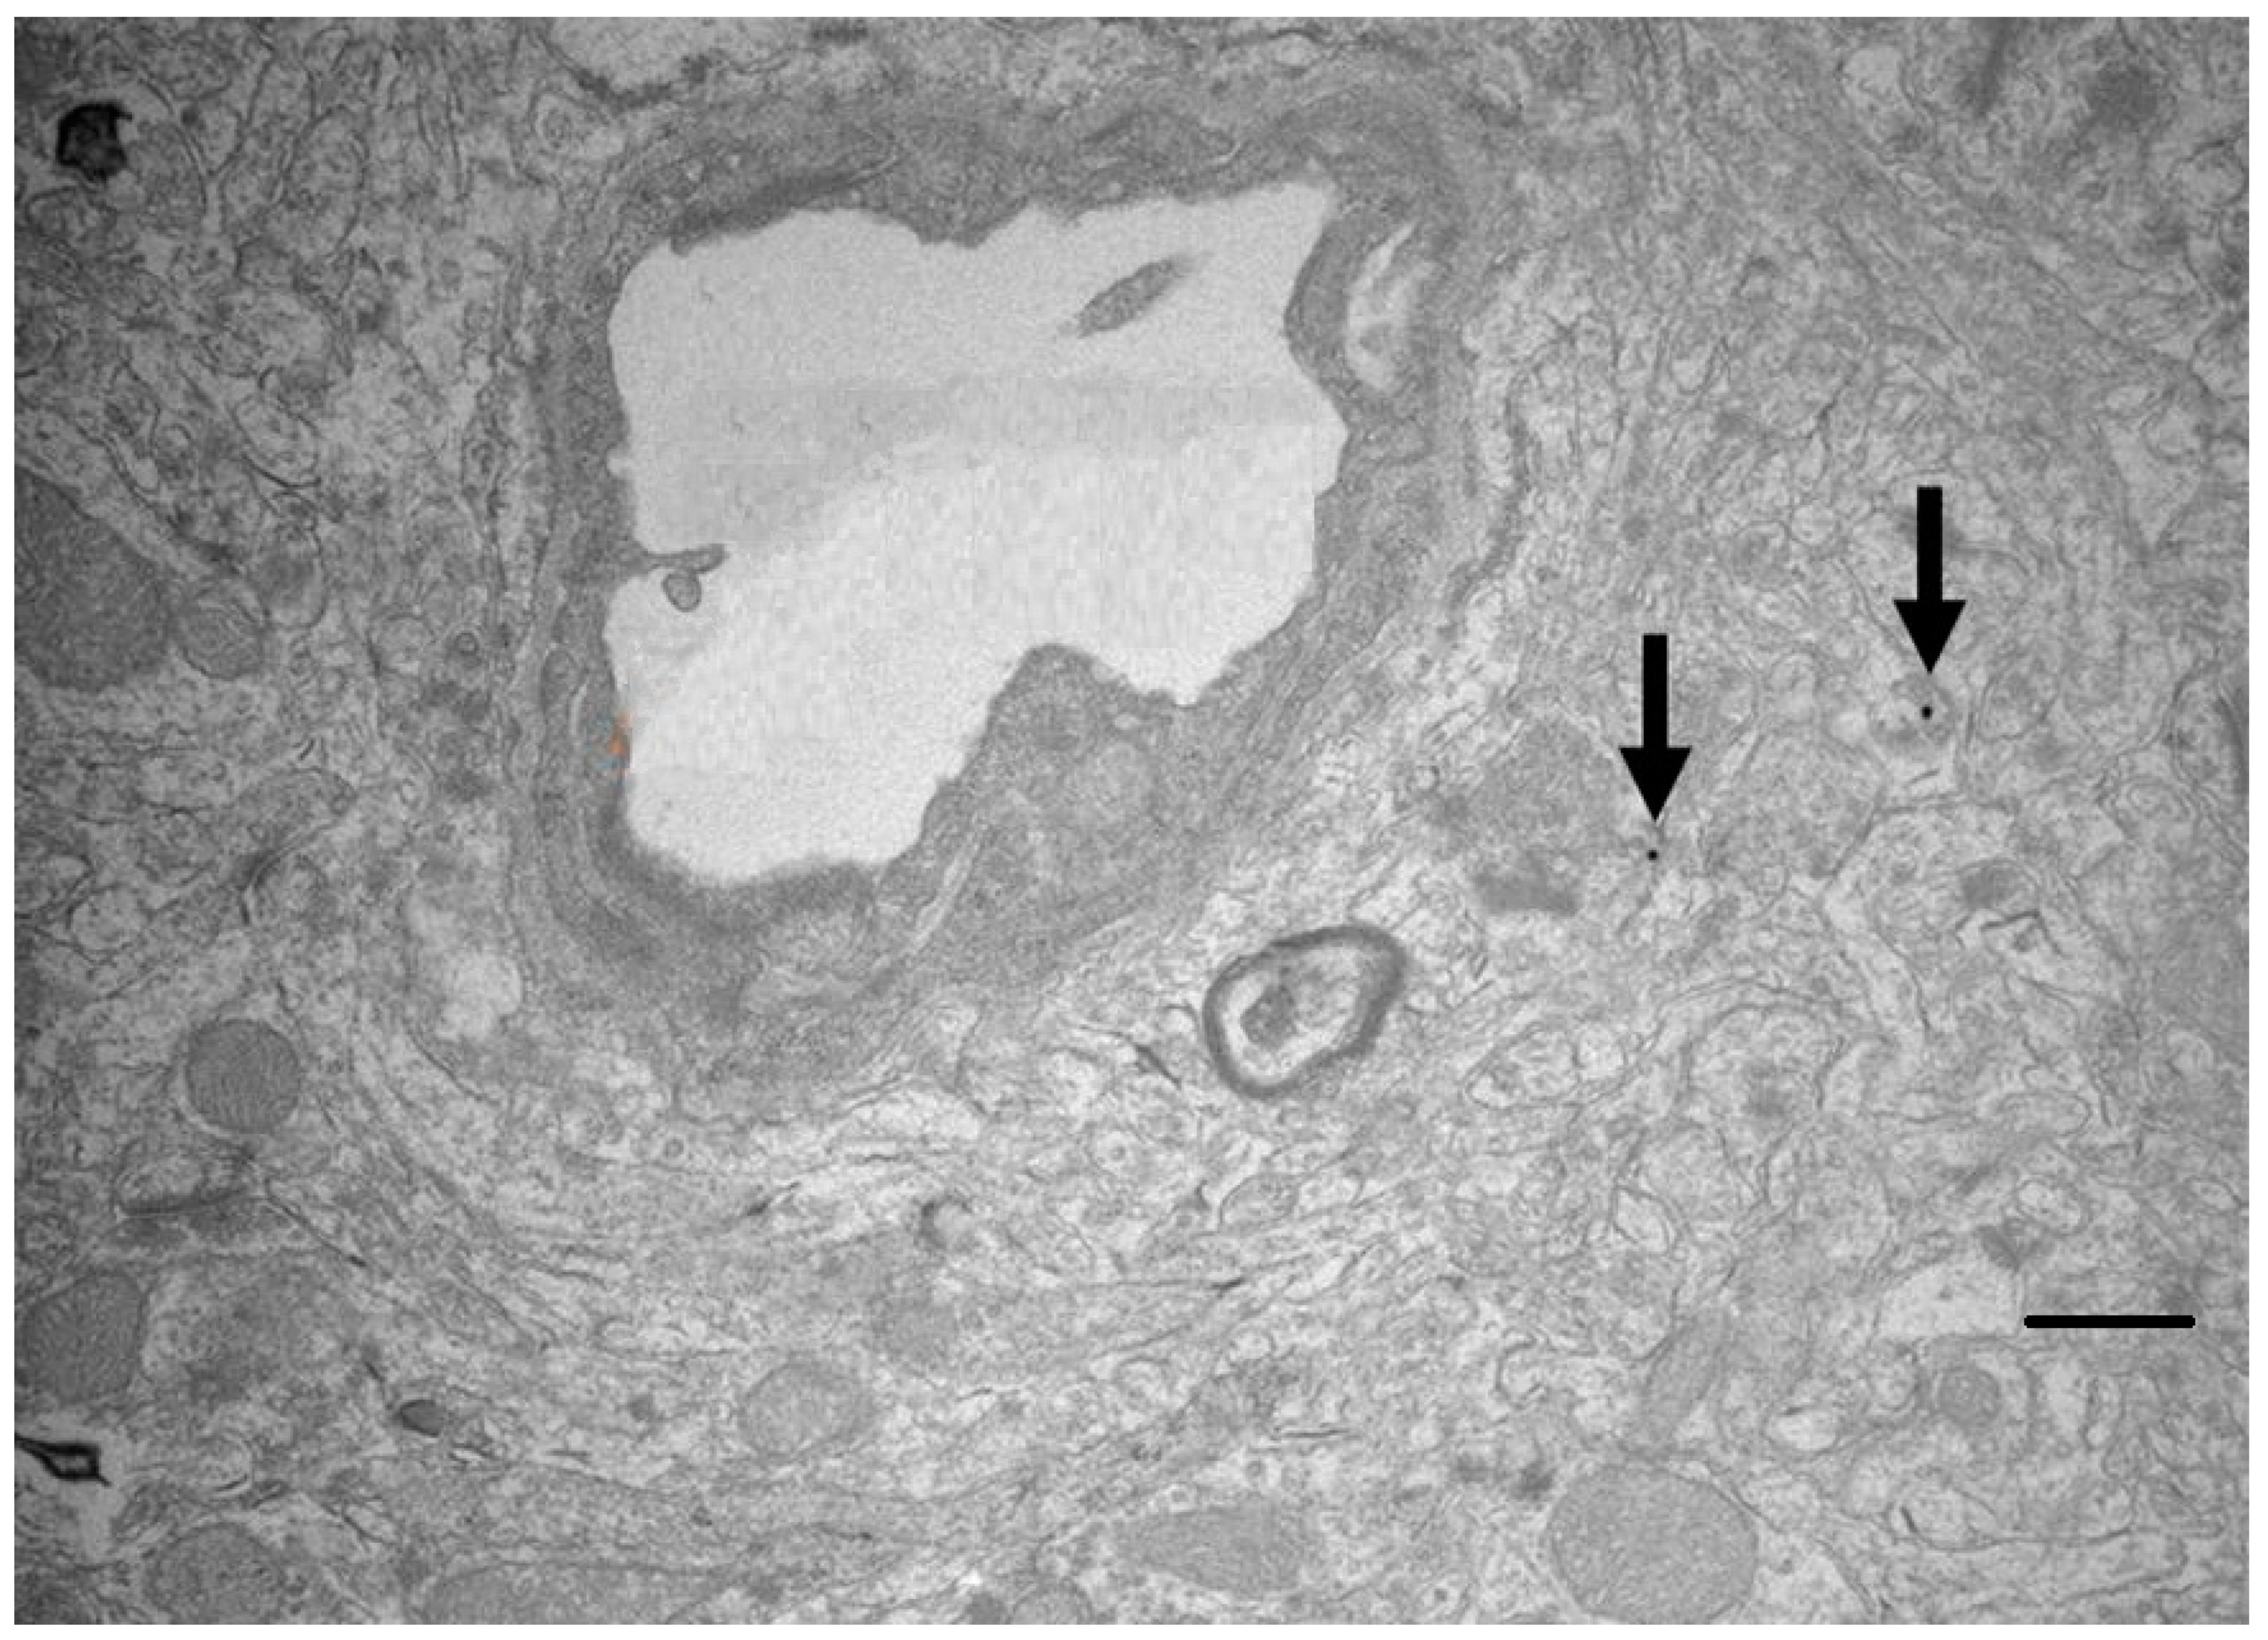

- Gromnicova, R.; Yilmaz, C.U.; Orhan, N.; Kaya, M.; Davies, H.; Williams, P.; Romero, I.A.; Sharrack, B.; Male, D. Localisation and mobility of glucose-coated gold nanoparticles within the brain. Nanomedicine 2016, 6, 617–625. [Google Scholar] [CrossRef] [Green Version]

- Fatima, N.; Akcan, U.; Kaya, M.; Gromnicova, R.; Loughlin, J.; Sharrack, B.; Male, D. Tissue distribution and cellular localization of gold nanocarriers with bound oligonucleotides. Nanomedicine 2021, 16, 709–720. [Google Scholar] [CrossRef]